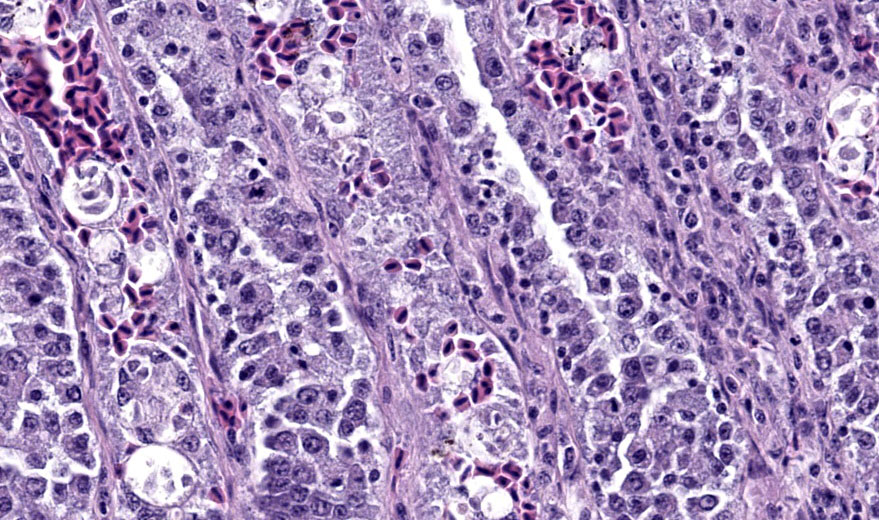

Liver: Surrounding portal regions and occasionally coalescing are infiltrates of moderate numbers of lymphocytes and histiocytes that disrupt the hepatic architecture. Within the lymphocytes and histiocytes are numerous, 2 um in diameter, basophilic protozoal organisms surrounded by a thin, clear halo that peripheralizes the nucleus. The inflammatory cells separate and individualize the hepatocytes, which display mild karyomegaly and frequent binucleation. Free within the sinusoidal lumina and within portal and central veins are numerous, approximately 5 um diameter, pyriform flagellate protozoa with a single, variably distinct nucleus. Occasional large lymphocytes and rare plasma cells circulate throughout the sinusoids.

Duodenum: The mucosal lamina propria is markedly infiltrated and expanded by numerous lymphocytes and histiocytes with rare plasma cells. The inflammatory cells broaden and occasionally fuse the villi and separate the intestinal crypts. Within the mononuclear cells are abundant 2 um diameter, basophilic protozoal organisms surrounded by a thin, clear halo that peripheralizes and indents the nucleus. The crypt epithelial cells are often pyknotic and sloughed into the lumen. Epithelial cells at the crypt bases are often hyperplastic, piling three to four cells thick with increased numbers of mitotic figures. The coelomic fat surrounding the duodenum has small, multifocal aggregates of lymphocytes.

Present in often very large numbers throughout the vasculature were extracellular protozoa consistent with flagellates that could have contributed to the inflammation in some tissues. Using a trichomonad PCR assay, sequences with a closest match to Cochlosoma anatis were obtained from both lung and intestine, although identity was only ~93%. Electron microscopy of liver tissue confirmed intracellular protozoa consistent with Isospora, and extracellular flagellates consistent with tetratrichomonads based on the presence of 5 undulipodia at the apical pole with one recurrent. In contrast, Cochlosoma sp. have six flagella, one of which is recurrent. Both Cochlosoma and Trichomonas have a single nucleus, a parabasal apparatus, a tubular axostyle, and a crescent-shaped pelta.6 Prior studies have identified via sequence analysis of the 16S rRNA gene that Cochlosoma and Trichomonas are genetically similar, which likely accounts for the 93% identity match.4Tetratrichomonas and C. anatis are often identified with other intestinal pathogens and their pathogenicity as a sole pathogen remains uncertain.1,4 Both have been documented as the cause of fulminant disease in a variety of birds. Tetratrichomoniasishas been identified as the causative agent of acute typhlohepatitis in ducks, a necrotizing hepatitis and splenitis in a Waldrapp ibis and necrotizing hepatitis in a free-ranging white pelican.1,2Cochlosoma anatis is linked to enteritis in turkeys, as well as increased dehydration, malabsorption, and mortality in young finches.4 However, prior studies have failed to document clinical signs or histologic lesions in experimental infections with Trichomonas and coinfections of Cochlosoma with other intestinal pathogens have demonstrated greater pathogenicity than with either pathogen alone.1,4

Many thanks to this contributor for an interesting case and well-written comment! It has been a while since the WSC saw a case of atoxoplasmosis (WSC 2009, Conf 18, Case 3), and this case provided some excellent discussion points. This was a challenging slide for many participants due to the lymphoproliferative nature of this protozoal infection, which, depending on the severity of the infection and the species affected, can be confused with lymphoma caused by gallid herpesvirus-2 (Marek?s disease), and avian retrovirus (lymphoid leukosis), etc.3 This was true in this conference, and some participants wondered about a lymphoma as the primary disease with the protozoa being secondary. The Isosporaserini were easier for the participants to find in this collection of tissue, but finding the flagellates, (Cochlosoma anatis) proved more difficult on the Hand E section (however, once the first flagellate were identified, participants were able to find them with ease.) Flagellates have a small, pinpoint nucleus and piriform shape, which differentiates them from mucin and debris. The group decided that there was not definitive evidence of cryptosporidia on the section of bursa, but only a very limited area of bursal epithelium (which cryptosporidia invade) was present in the section, so sampling was extremely limited.